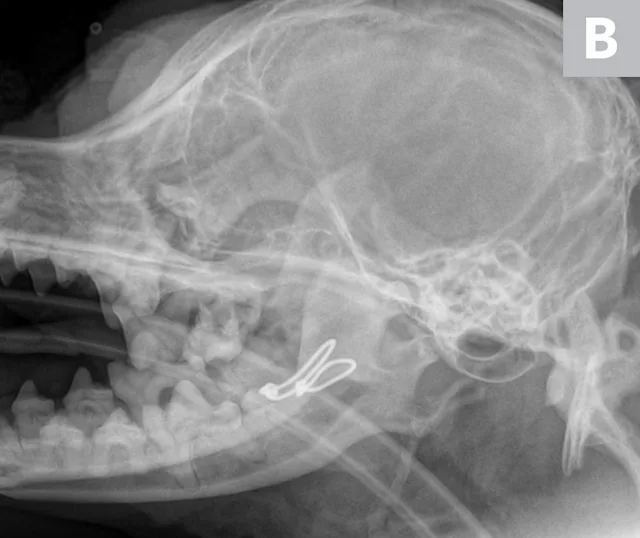

Lateral skull x-ray of dog with endotracheal tube in place and radiopaque cerclage wire around base of mandibular canines.

FIGURE 2

Lateral radiograph showing placement of a mandibular symphyseal wire in a dog